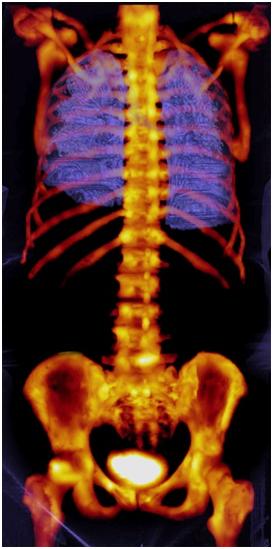

The Symbia Intevo™ from Siemens Healthcare integrates SPECT and CT enabling a high level of image quality and the ability to differentiate between tissue boundaries in bone imaging.

The new Symbia Intevo xSPECT system reconstructs both the SPECT and CT portions of an image into a much higher frame of reference than other systems for precise, accurate alignment facilitating the extraction and deep integration of medically relevant information. This ability is the basis for differentiating between tissue boundaries in bone imaging. With xSPECT Bone clinicians can potentially provide additional support for detection and distinguishing between cancerous lesions and degenerative disorders. The Symbia Intevo’s precise alignment of SPECT and CT provides clinicians with essential volumetric information from the CT scan, enabling accurate and consistent quantitative assessment meaning the clinician can apply quantitative information to assess whether a patient's condition has regressed, stabilised or progressed.